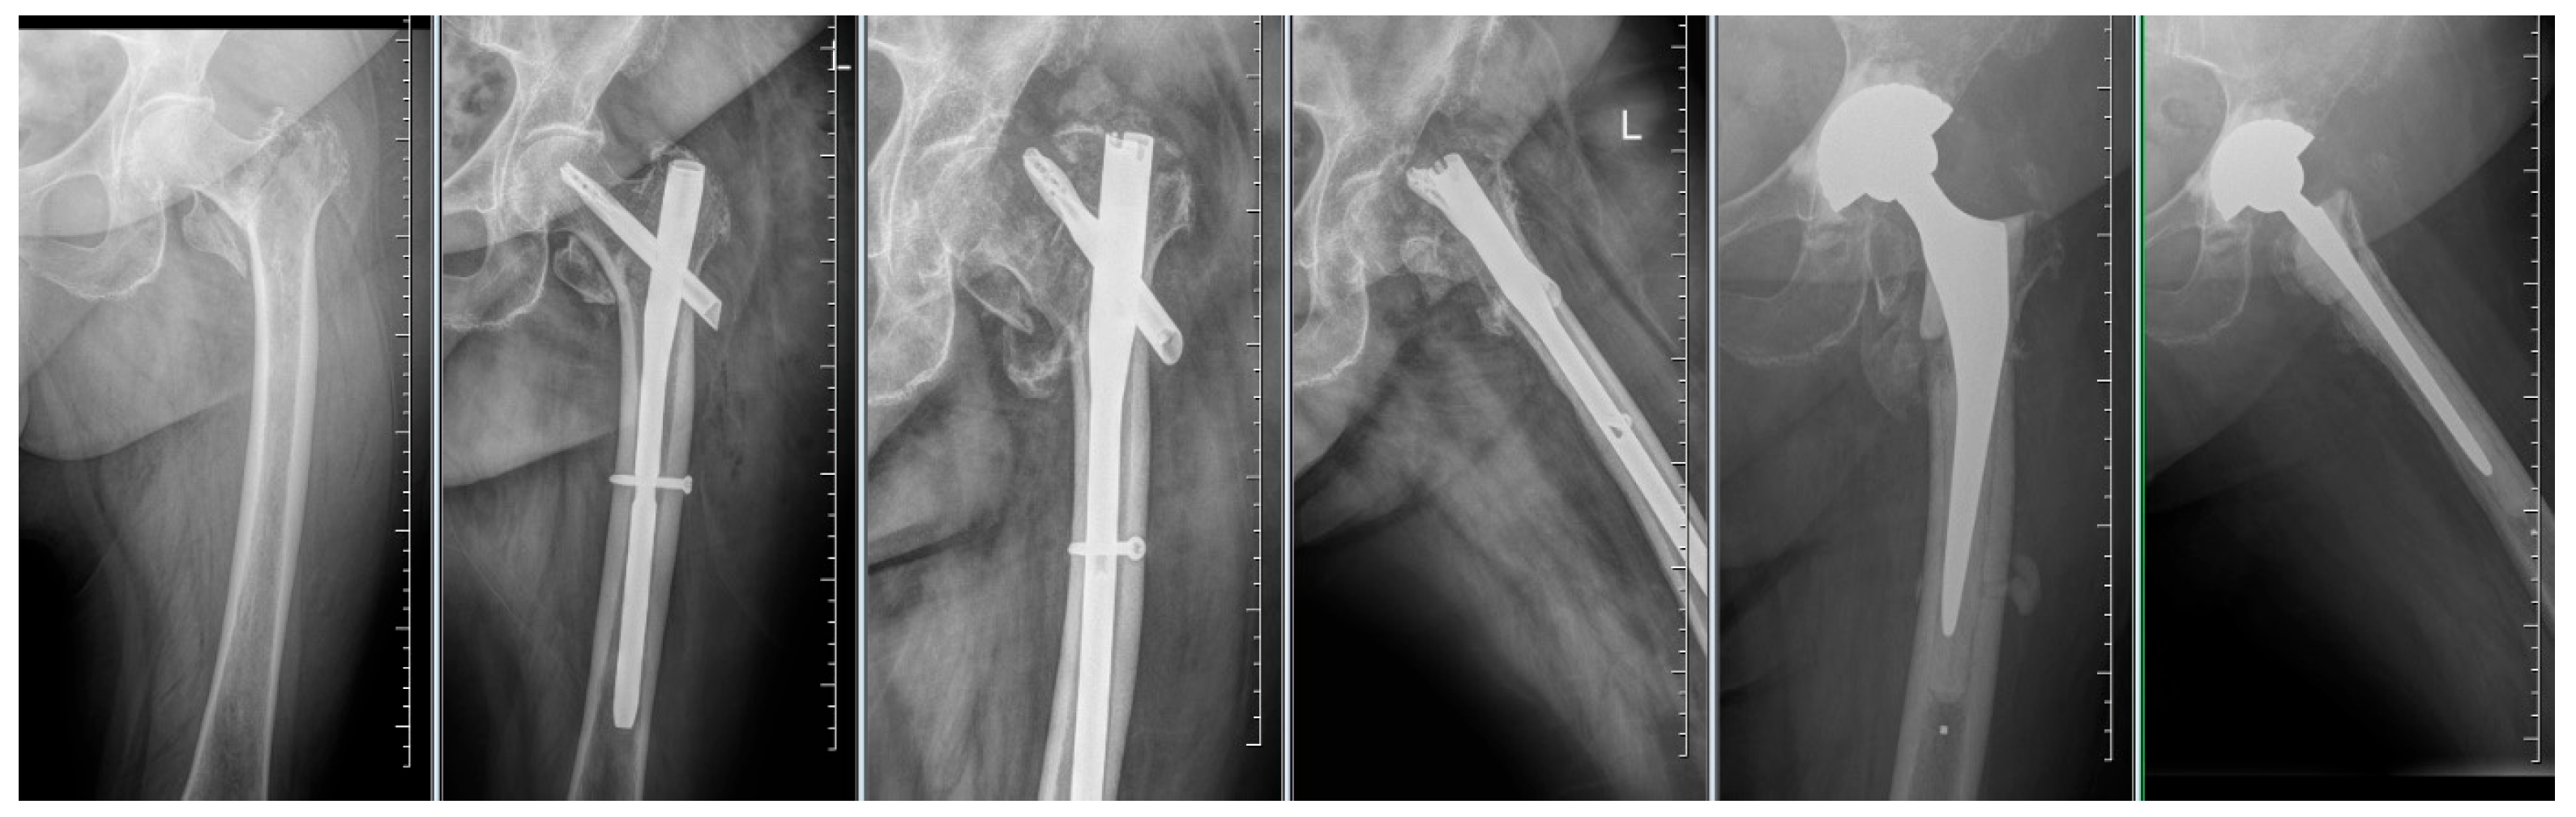

From clear X-ray images of the pelvis, the collum-diaphyseal (CCD) angle on the contralateral side before surgery was evaluated (Figure 1). From the same X-ray images, the type of fracture according to the AO/OTA classification was determined. After surgery, the following in AP projections were evaluated: CCD angle, fracture shortening, the distance between the tip of the blade and the subchondral bone, known as TAD (tip-apex distance) in two projections, the distance between the lateral end of the blade and the nail, and the position/course of the blade in the femoral head. TAD was calculated according to Baumgaertner’s description [9]. The position of the blade in the femoral head was determined based on the work of Cleveland [10]. The quality of reduction by evaluating the medial cortical line was assed, where we assessed both the disrupted continuity and displacement of fragments or the presence of a gap along this line. If the dislocation or gap was greater than 3 mm, the reduction in the area of the medial cortical line (Adam’s arc) was assessed as non-anatomical.

Figure 1. Standard projections and evaluated parameters: CCD angle (blue), TAD (red), blade course/position (yellow), lateral blade prominence (orange), anteversion (burgundy), and anterior cortical line and medial cortical line (green).